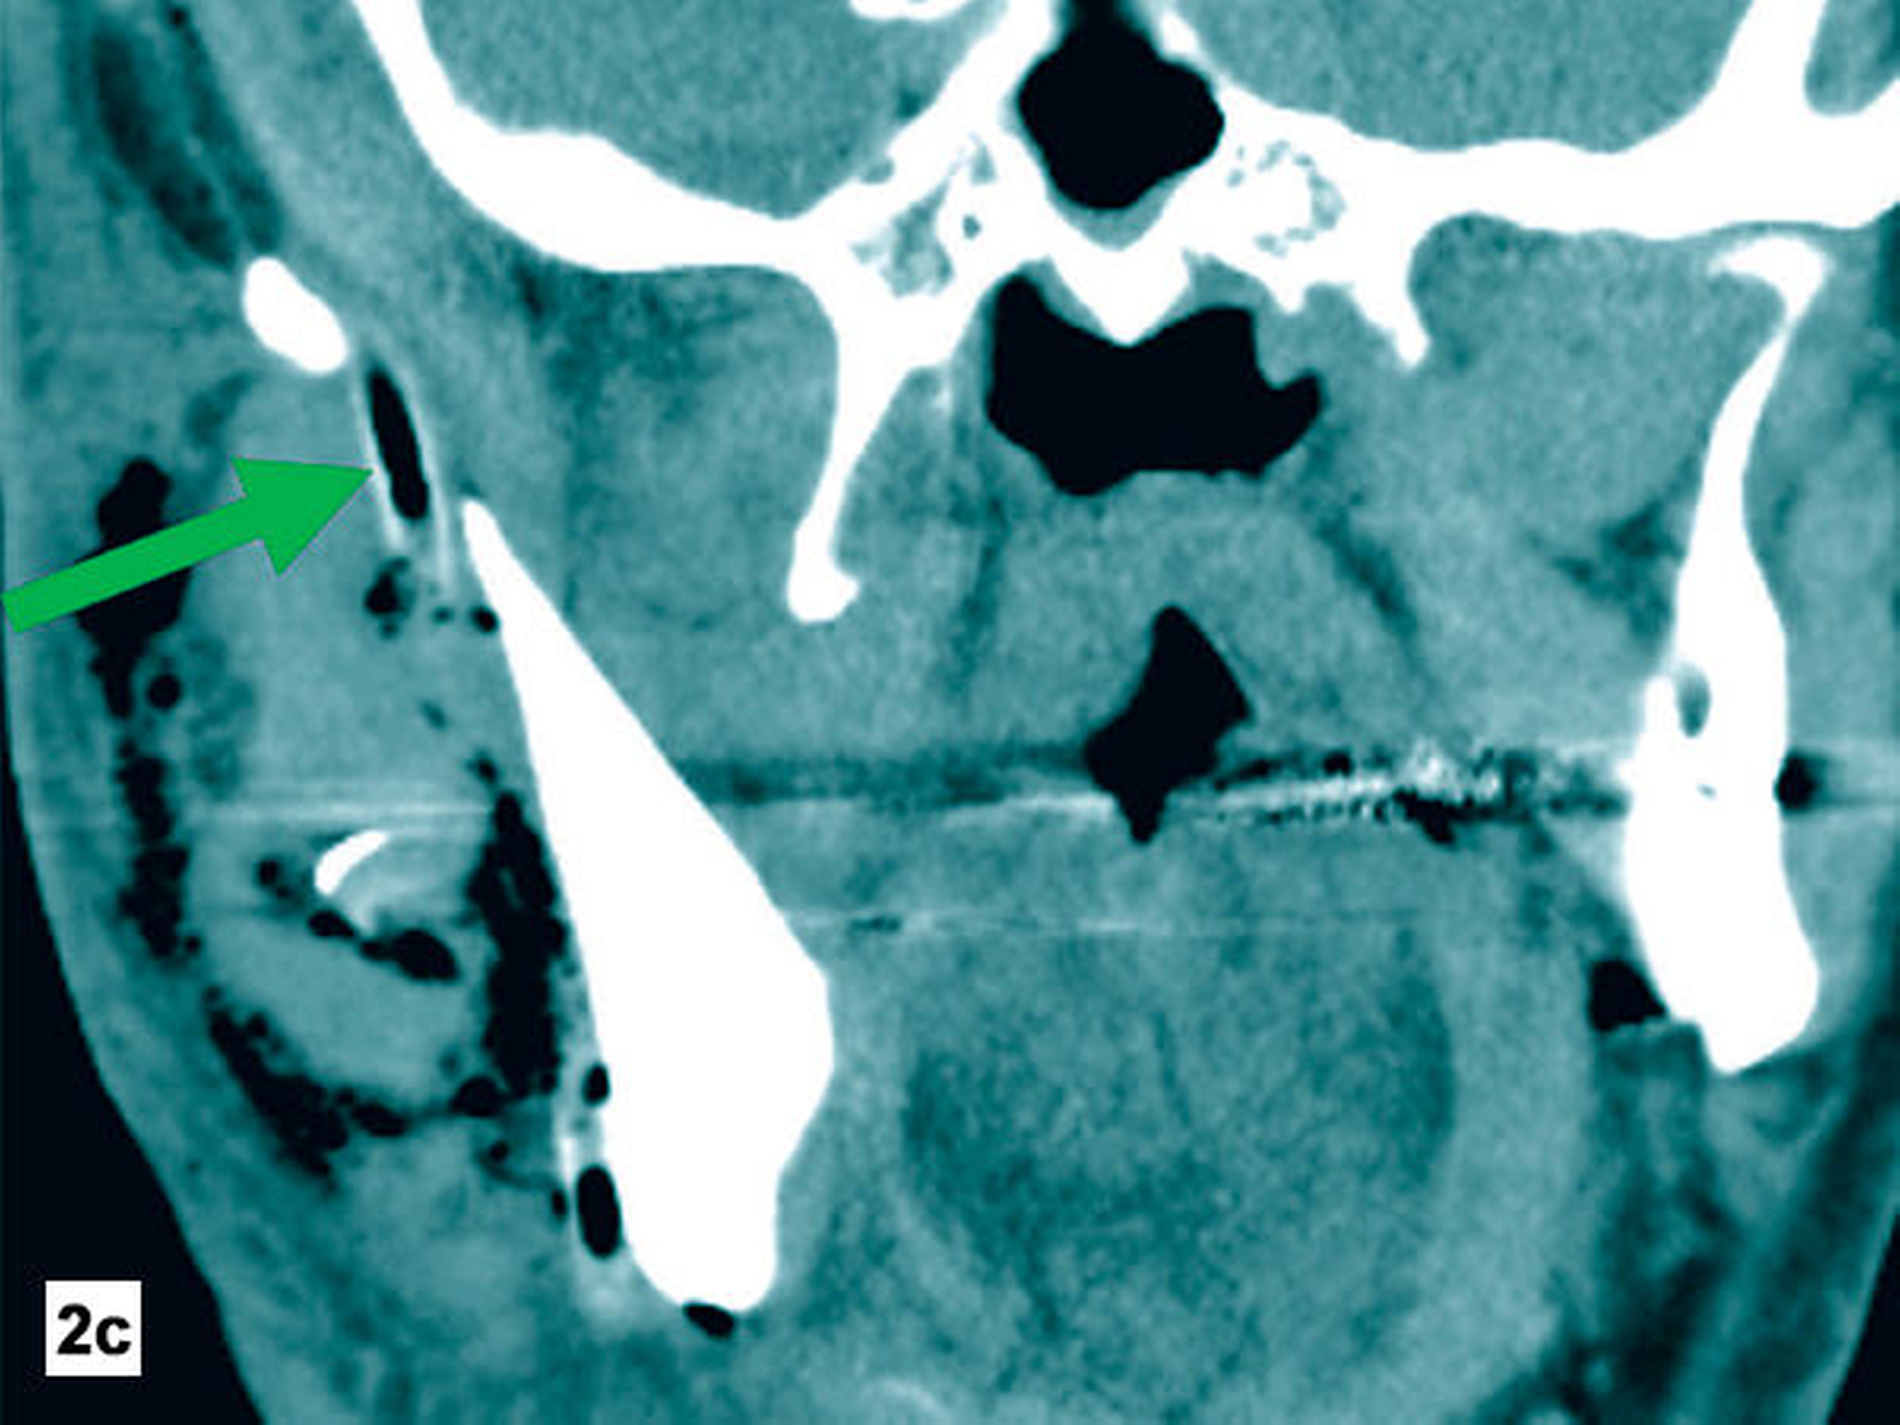

Am Folgetag zeigte der Patient eine zunehmende Verschlechterung und eine progrediente Schwellung der Halsregion mit beginnender Luftnot. Zur erweiterten Diagnostik wurde eine Computertomografie (CT) der Kopf-Hals-Region durchgeführt (Abbildung 2). Hier zeigten sich ein Flüssigkeitsverhalt submandibulär rechts trotz loco typico einliegender Drainage sowie Gewebseinschmelzungen und Gasblasen entlang des rechtsseitig-zervikalen und temporalen Faszienverlaufs.

Zur Diagnostik wird eine Schnittbilddiagnostik, in der Regel eine Computertomografie, empfohlen. Hierbei zeigen sich, wie im hier vorliegenden Fall, typischerweise Luftansammlungen und Gewebseinschmelzungen. Die Abgrenzung von Kutis und Subkutis ist regelhaft nicht mehr möglich [Kämmerer et al., 2017]. Das Vorliegen einer nekrotisierenden Fasziitis kann zusätzlich mit dem „Laboratory Risk Indicator for Necrotizing Fasciitis Score“ (LRINF) eingeschätzt werden, der positiv-prädiktive Wert wird in fortgeschrittenen Stadien mit 92 Prozent angegeben [Wong et al., 2004].